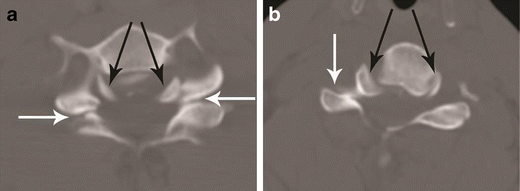

Bilateral versus unilateral facet joint dislocation. a Axial CT of the C5–C6 facet joint shows bilateral facet joint dislocation, suggested by reversal of the normal facet relationship, with convex surfaces opposing each other—called the “reverse hamburger sign” (white arrows). Loss of concentric relationship of the uncinate processes (black arrows) to the superior vertebral body—called the “positive headphone sign”. b Axial CT of the C4–C5 facet joint shows unilateral right-sided facet joint dislocation, suggested by a “naked facet” (white arrow)—due to absence of the opposing facet joint articular process because of dislocation. Loss of concentric arrangement of the right uncinate process (black arrows) due to rotation of vertebral body to the undislocated left side, resulting in unilateral positive “headphone sign”—suggesting rotational deformity